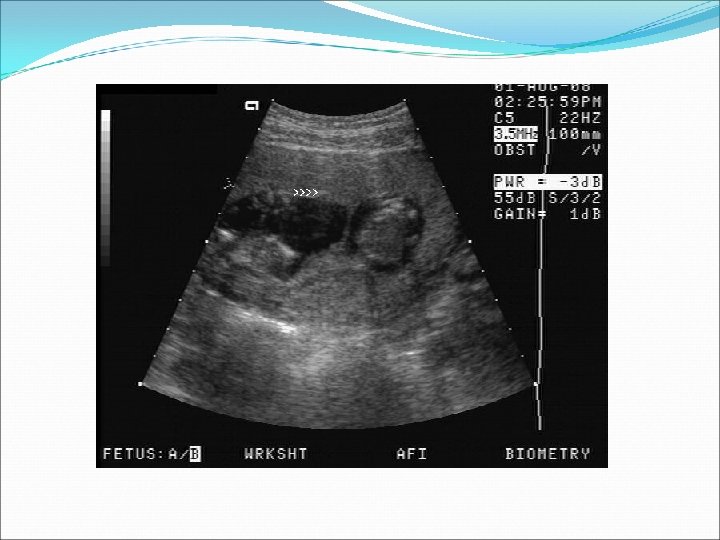

Ø Auscultation of two fetal heart beats at two different sites with a difference of 10 beats Ø USS Two sacs by 5 weeks by TV USS. Two embryos by 7 weeks by TV USS.